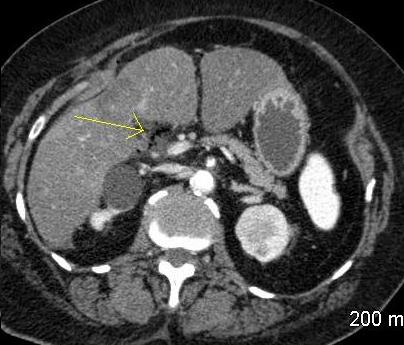

Ulcere gastro duodenal perfore : Image

TDM en coupe axiale |

Meme cas en coupe frontal ( coronal

) |